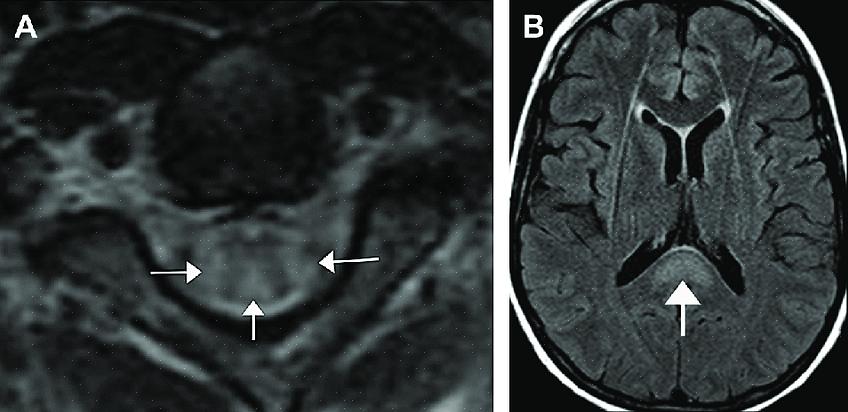

- ויטמין זה מייעל את תפקוד הנוירונים. אם יש לנו מחסור בוויטמין B12, יהיה לנו סיכון גבוה יותר לדמנציה, מה שמוביל לאלצהיימר (זכור, יש מתאם, אבל זה לא גורם ישיר).